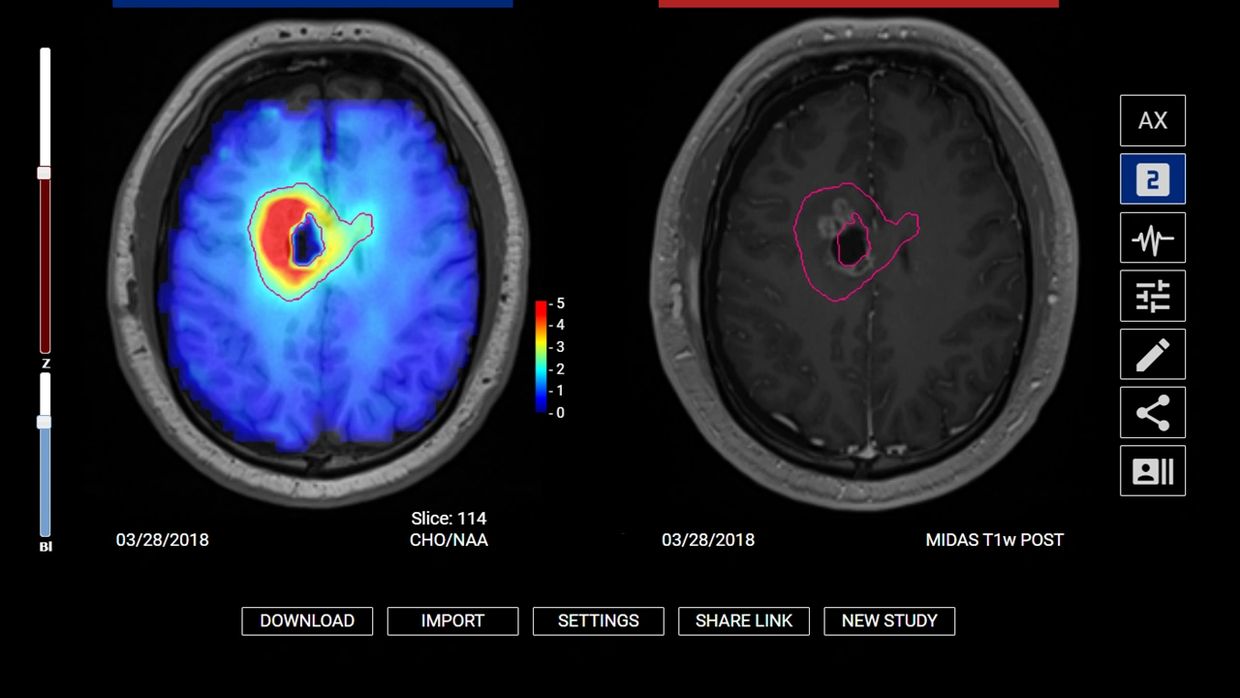

The BrIM AI platform has been used to guide surgical biopsies, radiation treatment, diagnose glioblastoma, and assess other diseases for adult and pediatric patients

Physicians at 3 institutions used BrIM AI to guide radiation treatment. Survival improved from 15 → 23 months, and tumor recurrence delayed from 5 -> 16 months; with minimal side effects